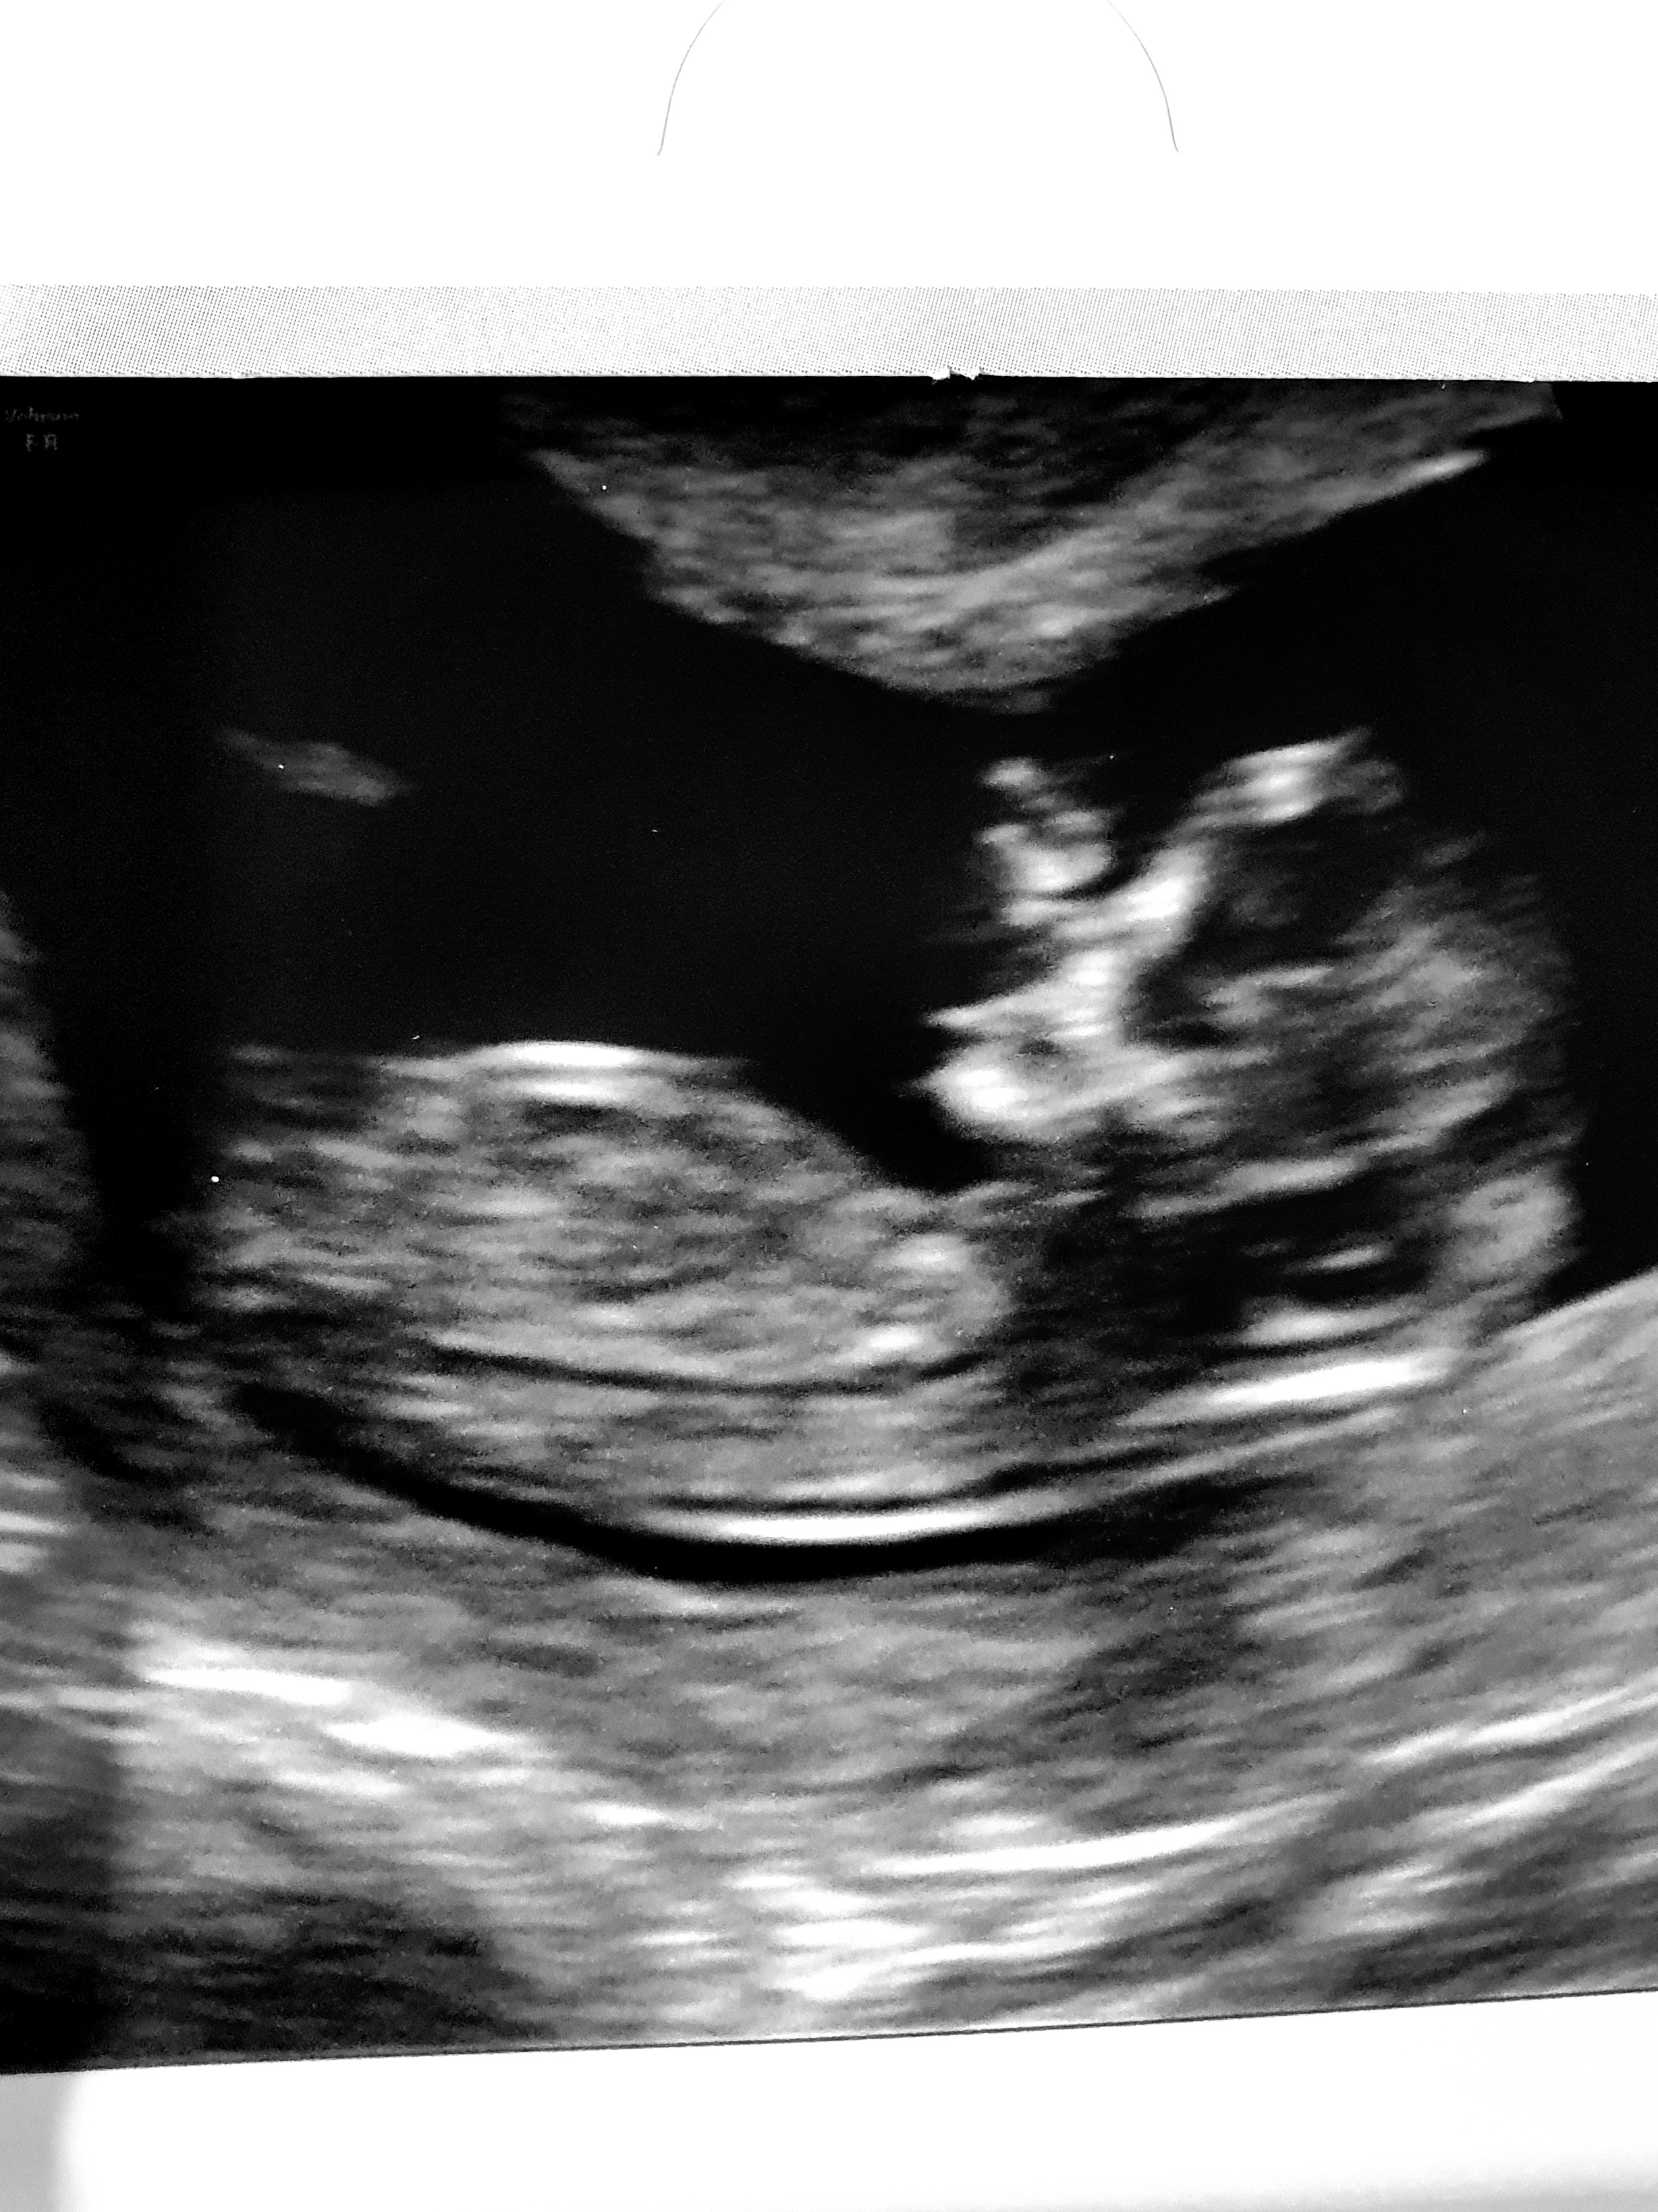

This one any better? X

The last pic looks boyish. I see what appears to be stacking on the nub.

Did you see the ‘sausage’ that he pointed out on the screen?? If it were just based on that picture I think I’d ask for a rescan to confirm as 4 weeks is a long time to wait.. it doesn’t look like a sausage to me but it could be the sausages Crown Jewels. At first I thought it looked like labia but looking again it looks slightly disconnected to the bottom area so could be cord... when I had my ds2 (didn’t find out with ds1) there was no doubt he was a boy.

He didn't point it out, basically ask what we thought then said he's already seen the sausage in a profile view (20 seconds into the scan).... i thought he may just be super experienced but now I'm having doubts. Its the separated bit that looks different, my other boys were so so obvious!